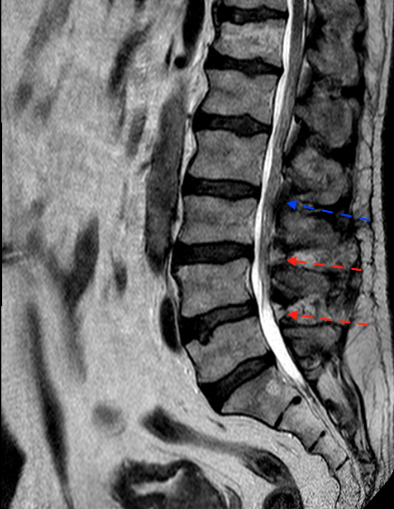

Las flechas rojas indican los niveles intervenidos. Obsérvese, comparando con niveles no intervenidos (flecha azul), la ausencia de ligamentos en espacio interespinoso e interlaminar

Postoperatorio

Los cambios postoperatorios son muy sutiles en la RM. Quizá en una RM dinámica (en bipedestación y extensión) pudieran apreciarse mejor.

En esta técnica hay que respetar la anatomía para no provocar una inestabilidad secundaria.